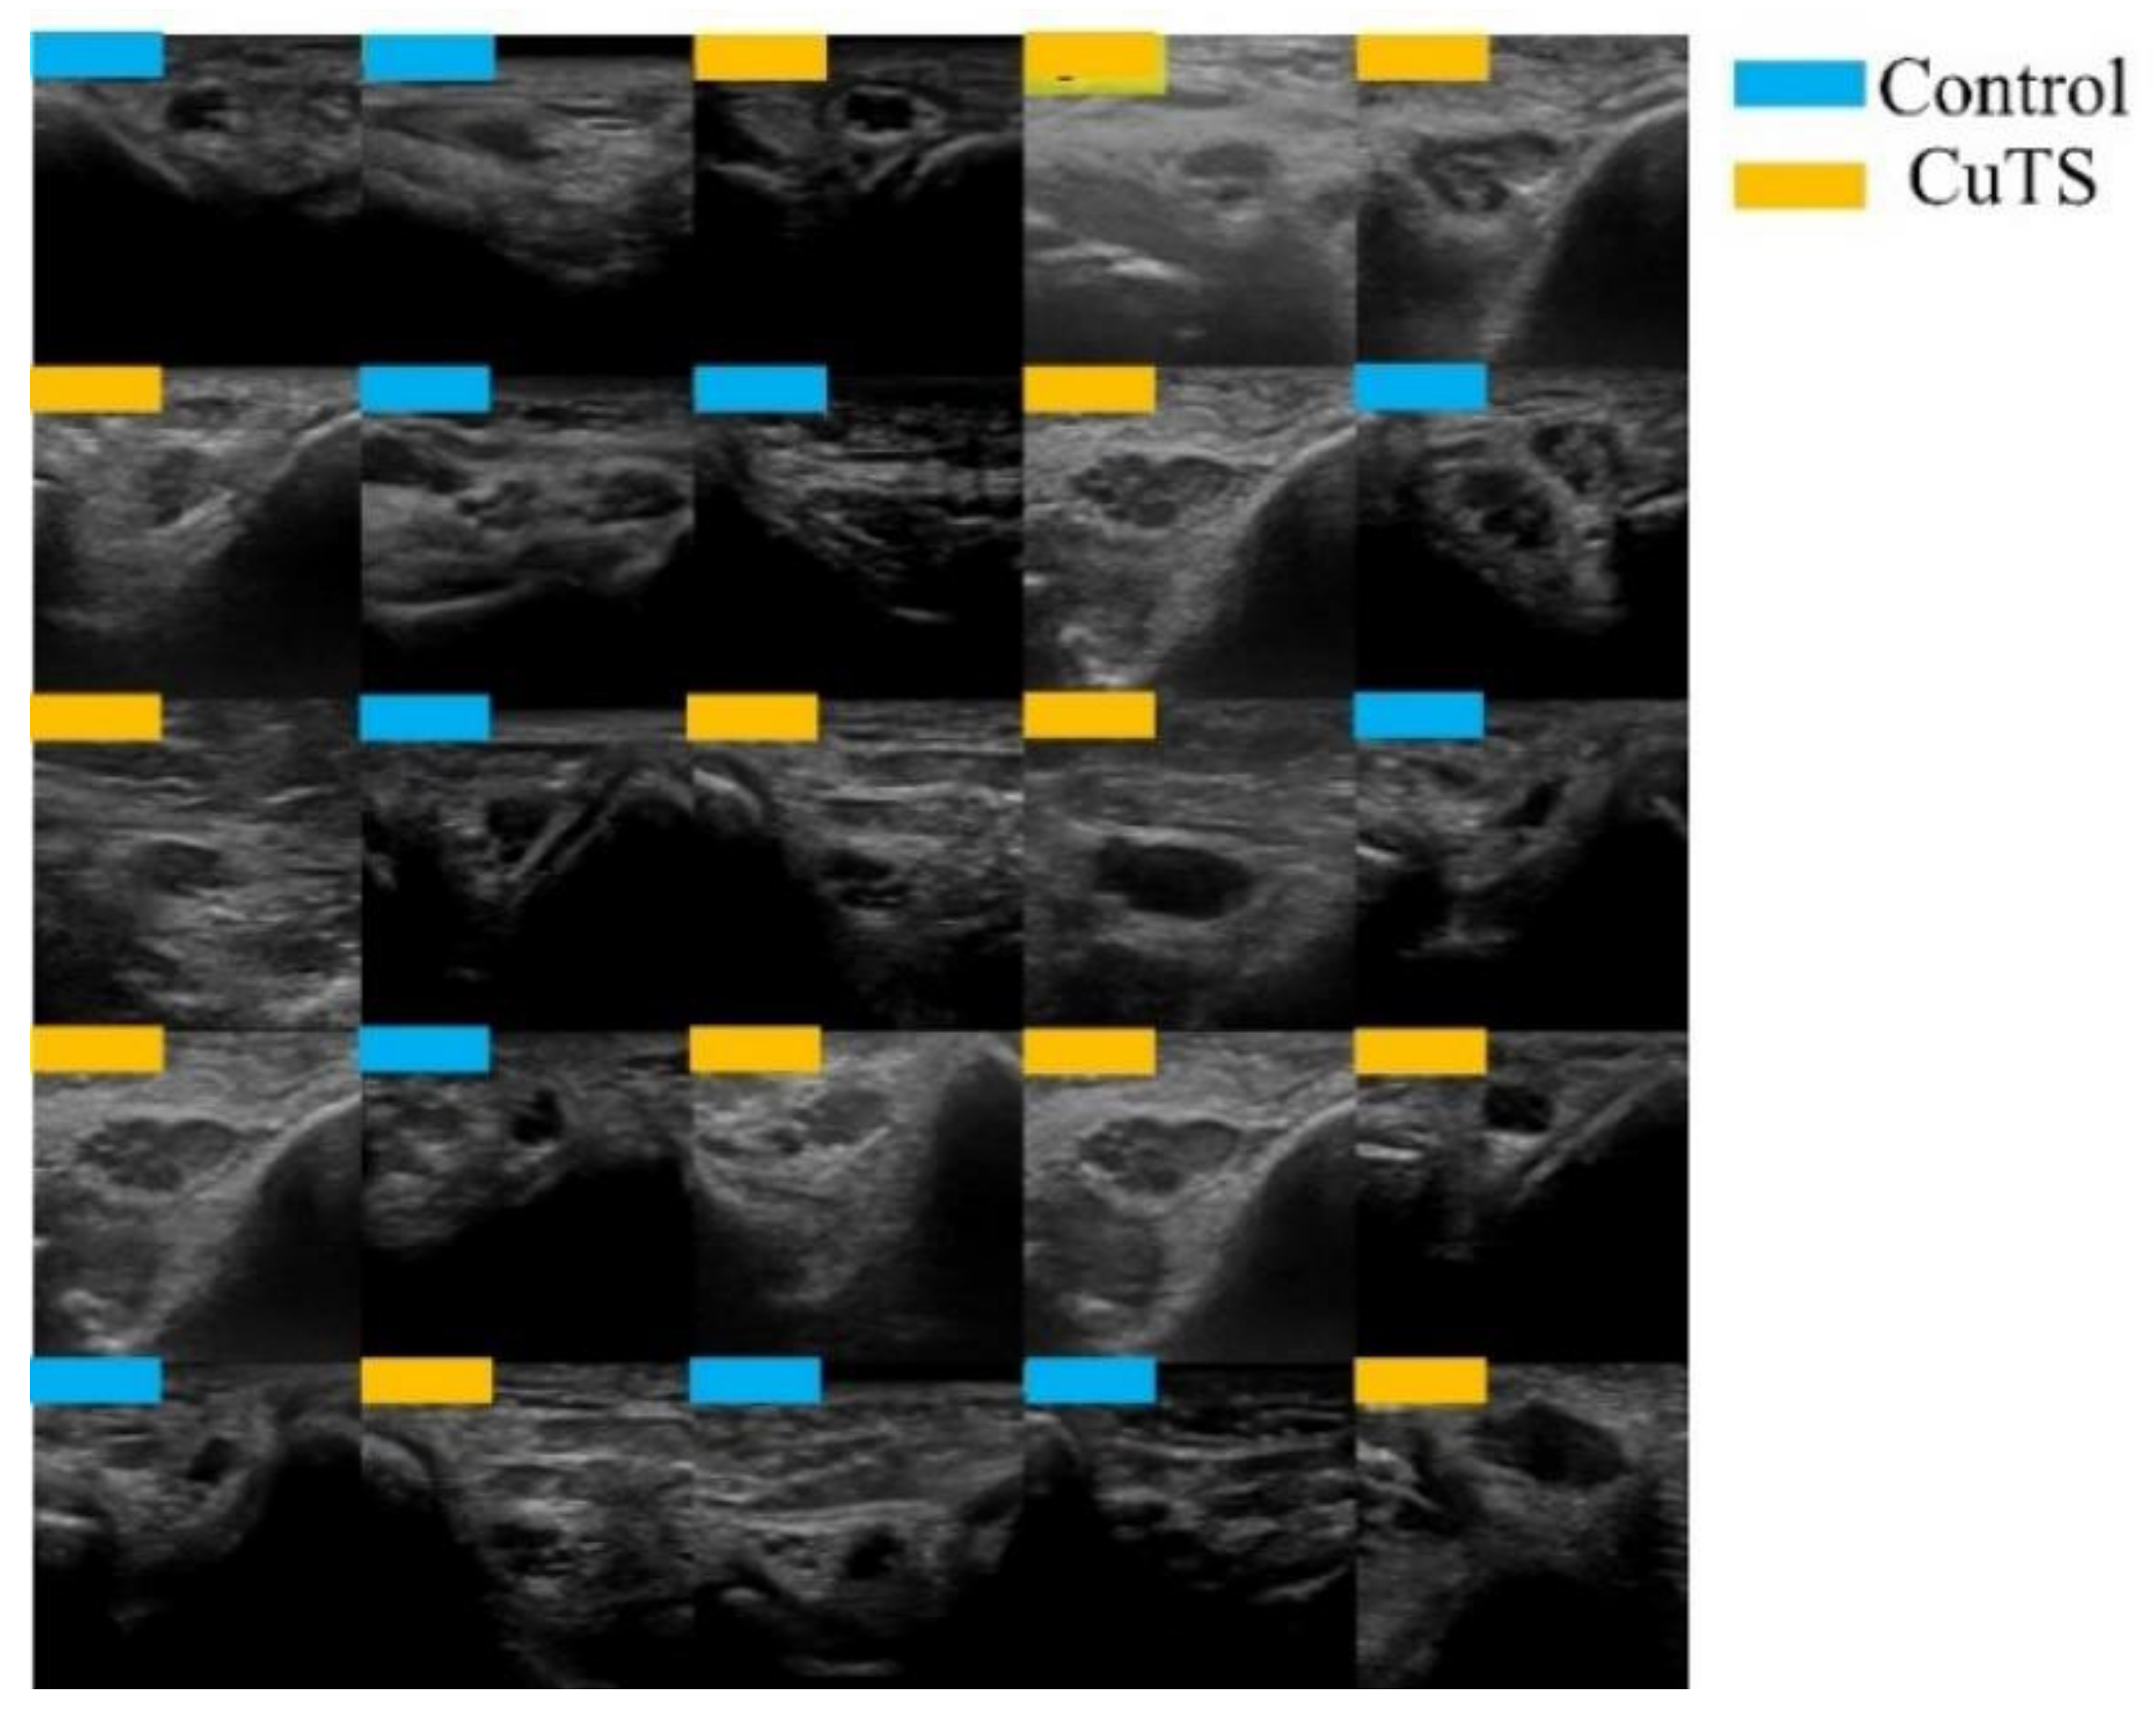

2.1. Data Selection

2.2. Data Augmentation